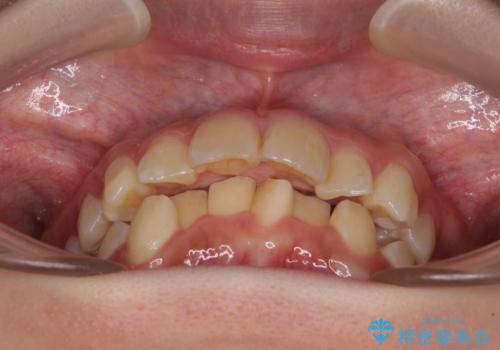

- 前方に飛び出した前歯と、下顎の八重歯を気にして来院された患者様です。

口元の突出感を改善するため、上下左右の第一小臼歯4本を抜歯し、ワイヤー装置にて矯正治療を行うこととしました。